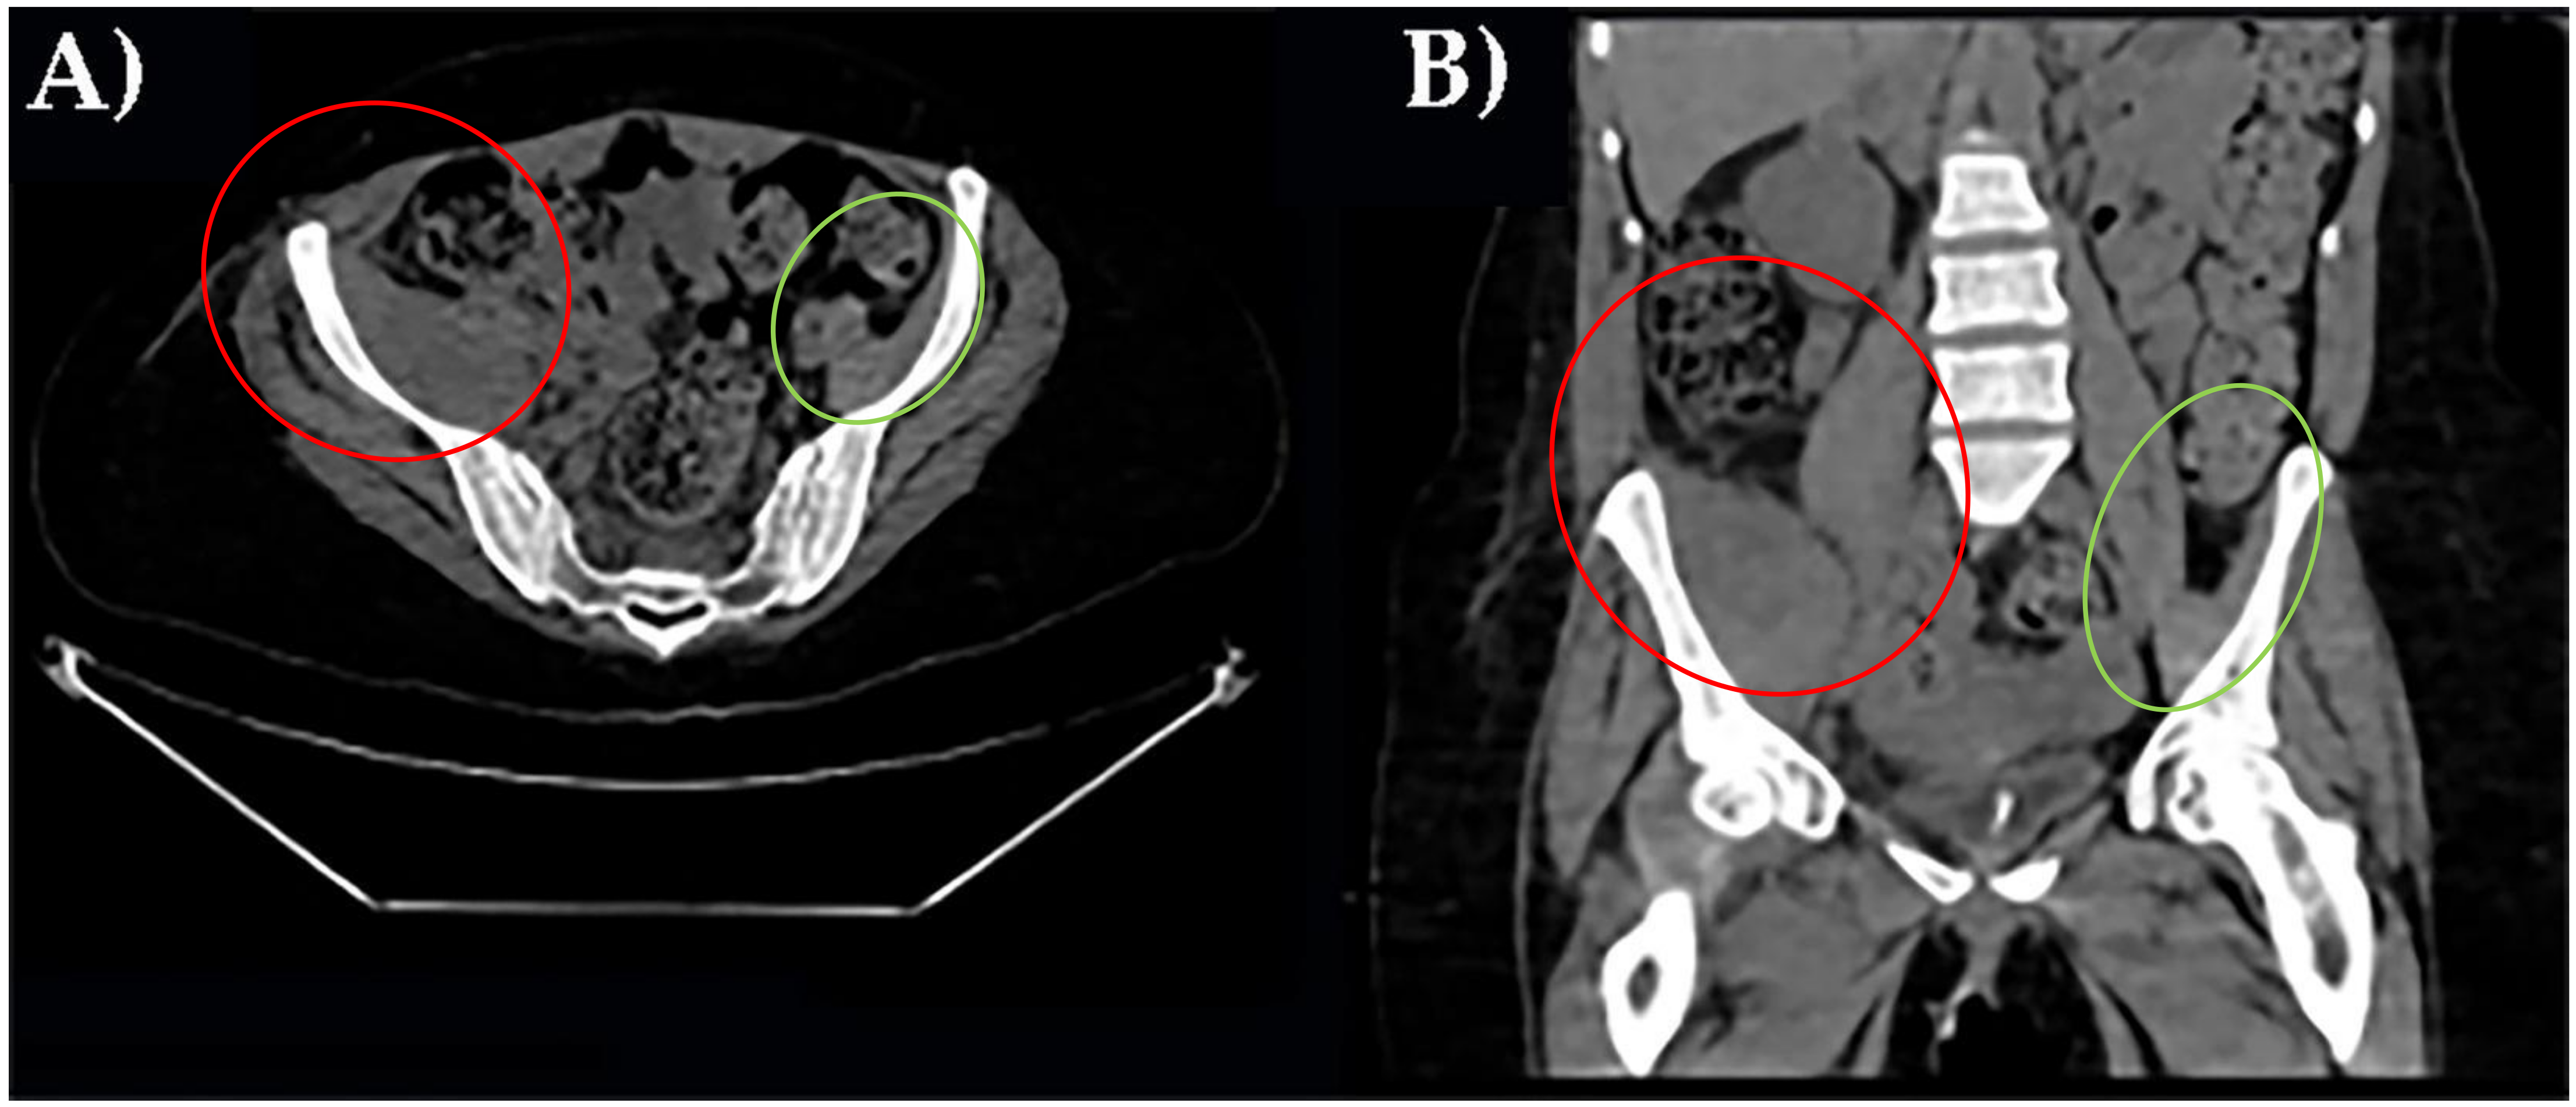

Finally, an MRI examination definitively revealed an iliac right muscle enlargement, hypo and hyperintensity muscle lesions on T2 sequences better seen on fat attenuation sequences (STIR), and partially extending to gluteal muscles group. This is a pattern indicative of muscle hematoma with different lesions at different stages (Figure 2).

Figure 2. MRI of the pelvis with right ileal muscle hematoma performed with a T1- (A), T2- (B), and STIR sequences (C). In red, pathological finding; in green, normal appearance.